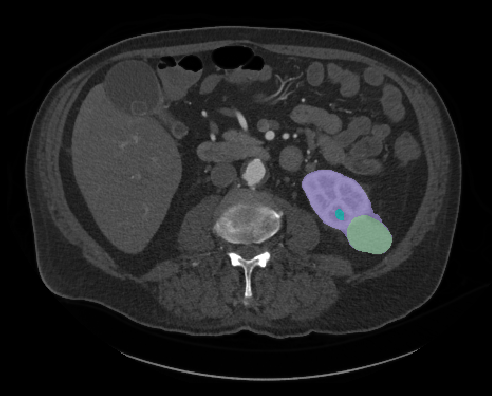

“Then we can turn those numbers into a computer code. If we can automate the code with images and equipment, a radiologist can just hit a button and receive information on the tumor, rather than looking at the image and making a judgement call,” Heller states.

Eventually, Heller hopes using data driven decisions will create useful tools for radiologists and aid in the discovery of visual biomarkers for non-invasive kidney cancer. Most importantly, the computer algorithms would help medical professionals become more effective in treating the disease and allow scientists to conduct more research based off the numerical patterns they see in each stage of the disease.

In 2019, Heller’s team organized a competition and released their vast data collection on kidney tumors to the public. Known as the Medical Image Computing and Computer-Assisted Intervention (MICCAI) Kidney Tumor Segmentation Challenge, or “KiTS,” Heller asked participants to design and train their own machine learning algorithm models using the data and parameters given to them. As it turns out, the UMN group’s segmented kidney cancer dataset was the first of its kind to be used in this type of competition—and drew a lot of interest in the medical community. “We had more than 100 teams from around the world participate in the challenge,” he says. “The event was held in conjunction with a conference in China, so there was a lot of international collaboration. It was a great experience.”

As the lead organizer, Heller and his team evaluated each entry, ranked them from most successful algorithmic designed model to least successful, and published the results on their website.